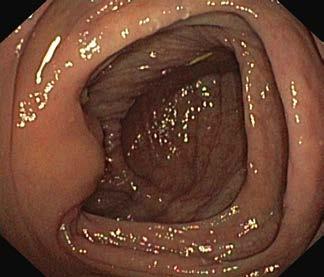

W kątnicy widoczny jest charakterystyczny układ fałdów

Choroby układu pokarmowego Ryc. III.B.4-33 Kolonoskopia. Prawidłowa błona śluzowa jelita gru bego – gładka, lśniąca, z widocznym rysunkiem naczyniowy m Ryc. III.B.4-34 Kolonoskopia. Prawidłowa kątnica; widoczna zastaw ka krętniczo ‑kątnicza (strzałka) i typowy układ fałdów